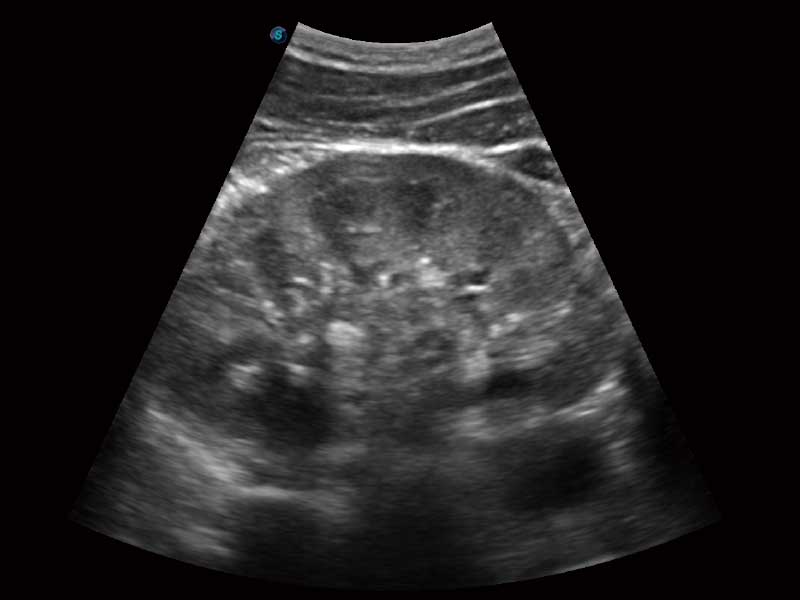

μ-Scan微米成像、空间复合成像、高分辨率血流成像。

单键操作,可快速优化多个二维及多普勒图像参数,获得优异图像效果。